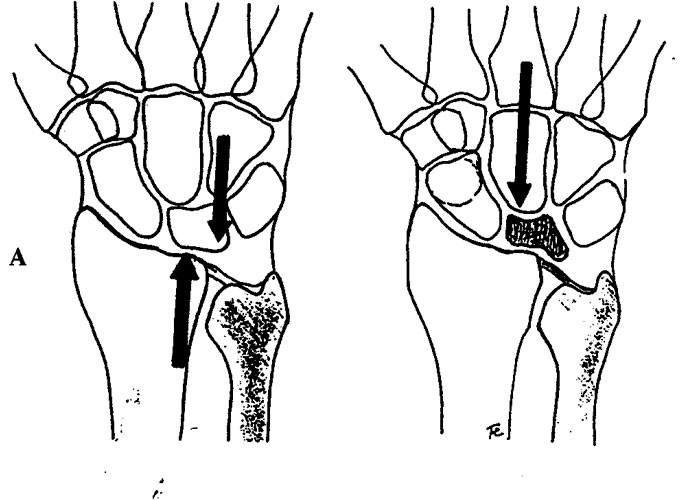

Alteraciones mecánicas o anatómicas, como una discrepancia en la longitud de los huesos: tener un cúbito corto (figuras 1 y 2) y una determinada forma anatómica de semilunar (tipo I) (figura 3).

Figuras 1 y 2: cúbito minus o corto (predisponente de Kienböck)

Figura 3: tipos de formas del semilunar. Mayor riesgo el tipo I con cúbito corto